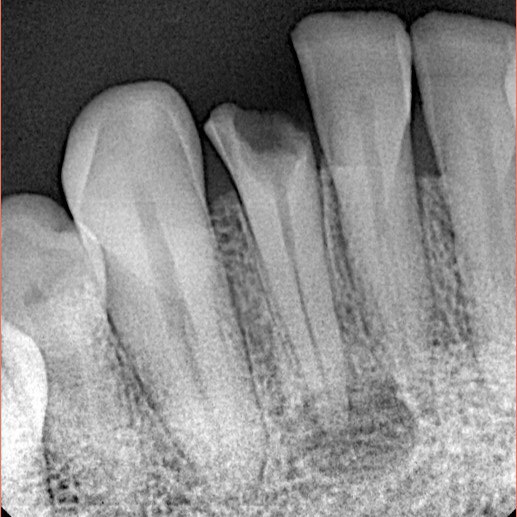

25 years old male had sport injury long period ago.

He Visited us because of pain in his fractured lower anterior tooth

Fractured Lower lateral incisor was necrotic and had periapical lesion as seen in X-ray